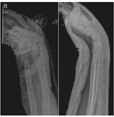

(1)手法复位组:牵引患儿前臂与腕部并旋转骨折远端纠正旋转移位,采用折顶复位纠正前后移位。在C型臂X线机透视下见骨折对位对线良好,予屈腕或背伸腕位肘下短臂前后石膏托外固定(图1)。